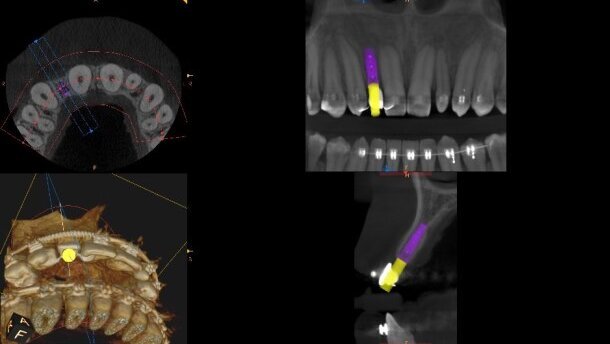

W przeszłości planowanie umieszczenia implantu dokonywało się na podstawie zdjęcia pojedynczego zęba lub zdjęcia panoramicznego, co obarczone było niską precyzją.5 Obecnie z pomocą przychodzą systemy, które pozwalają na wirtualne planowanie leczenia implantoprotetycznego z wykorzystaniem tomografii komputerowej wiązki stożkowej. CBCT jest techniką obrazowania medycznego, gdzie podstawą każdego badania są przekroje cyfrowe. Na podstawie tych przekrojów uzyskiwany jest obraz dwu- lub trójwymiarowy badanego obszaru.6 Zdolność oprogramowania komputerowego do przeformatowania cyfrowych tomogramów na obraz 2D i 3D z dokładnością wymiarów w stosunku 1:1 pozwala na dokładne zaplanowanie umiejscowienia implantu.7

W niniejszym artykule opisano zastosowanie 2 różnych możliwości oprogramowania: CS 3D Imaging Software, które pozwala na trójwymiarową ocenę diagnostyczną, wykonanie rekonstrukcji wybranego obszaru bez nakładania się struktur anatomicznych oraz na dokonanie pomiarów wyrostka zębodołowego przed planowanymi zabiegami implantologicznymi oraz oprogramowaniem DDS-PRO Implants. Przeznaczone jest ono do wsparcia procesu diagnostycznego, przygotowania do zabiegu implantologii stomatologicznej, wizualizacji 3D struktur kostnych oraz zaplanowania i symulacji zabiegu. Technika ta wykorzystuje dane z tomografii komputerowej wiązki stożkowej8 i umożliwia wykonanie specjalnej pokrywy na zęby o zadanej grubości, zwanej szablonem chirurgicznym lub prowadnicą wiertniczą, dzięki możliwości drukowania modelu z DDS-Pro w drukarce 3D. W miejscach, gdzie umieszczany będzie implant, prowadnica wiertnicza posiada nadlewy z otworem, w którym umieszczana jest tuleja wprowadzająca wiertło.

Pierwszy etap stanowiło leczenie ortodontyczne. Po 18 miesiącach uzyskano odpowiednie przestrzenie dla odtworzenia brakującego zęba 12 oraz zmiany kształtu siekacza bocznego lewego w szczęce. Przy obecności obu aparatów ortodontycznych rozpoczęto drugi etap leczenia. W znieczuleniu nasiękowym (Ubistesin Forte 4%) wszczepiono implant w miejscu zęba 12 przy stabilizacji na poziomie ponad 50 (Biomet 3i, 3,25 x 11,5 mm). Zabieg wykonano w osłonie antybiotykowej (Dalacin C 300 mg), a pozabiegowe zalecenia obejmowały: kontynowanie przyjmowania antybiotyku przez 7 dni 1 tabl. co 8 godz., stosowanie płukanki z zawartością 0,2% chlorheksydyny 3 razy dziennie, dietę miękką i w razie konieczności środki przeciwbólowe w postaci ibuprofenu w dawce 600 mg 3 razy dziennie. W celu jak najbardziej precyzyjnego umiejscowienia implantu wykorzystaliśmy oprogramowanie CS 3D Imaging Software.

Obecność odpowiedniej jakości i ilości kości jest niezbędna dla powodzenia zabiegu wszczepienia implantu. Do oceny czy istnieją odpowiednie warunki kostne oraz zaplanowania całego leczenia implantoprotetycznego wykorzystano systemy oparte na tomografii komputerowej wiązki stożkowej (CBCT). Oprogramowanie CS 3D Imaging Software pozwoliło wykonać trójwymiarową diagnostykę obszaru dla wszczepu implantologicznego. Dzięki pomiarom wyrostka zębodołowego możliwy był wybór odpowiedniego systemu i rozmiaru implantu.